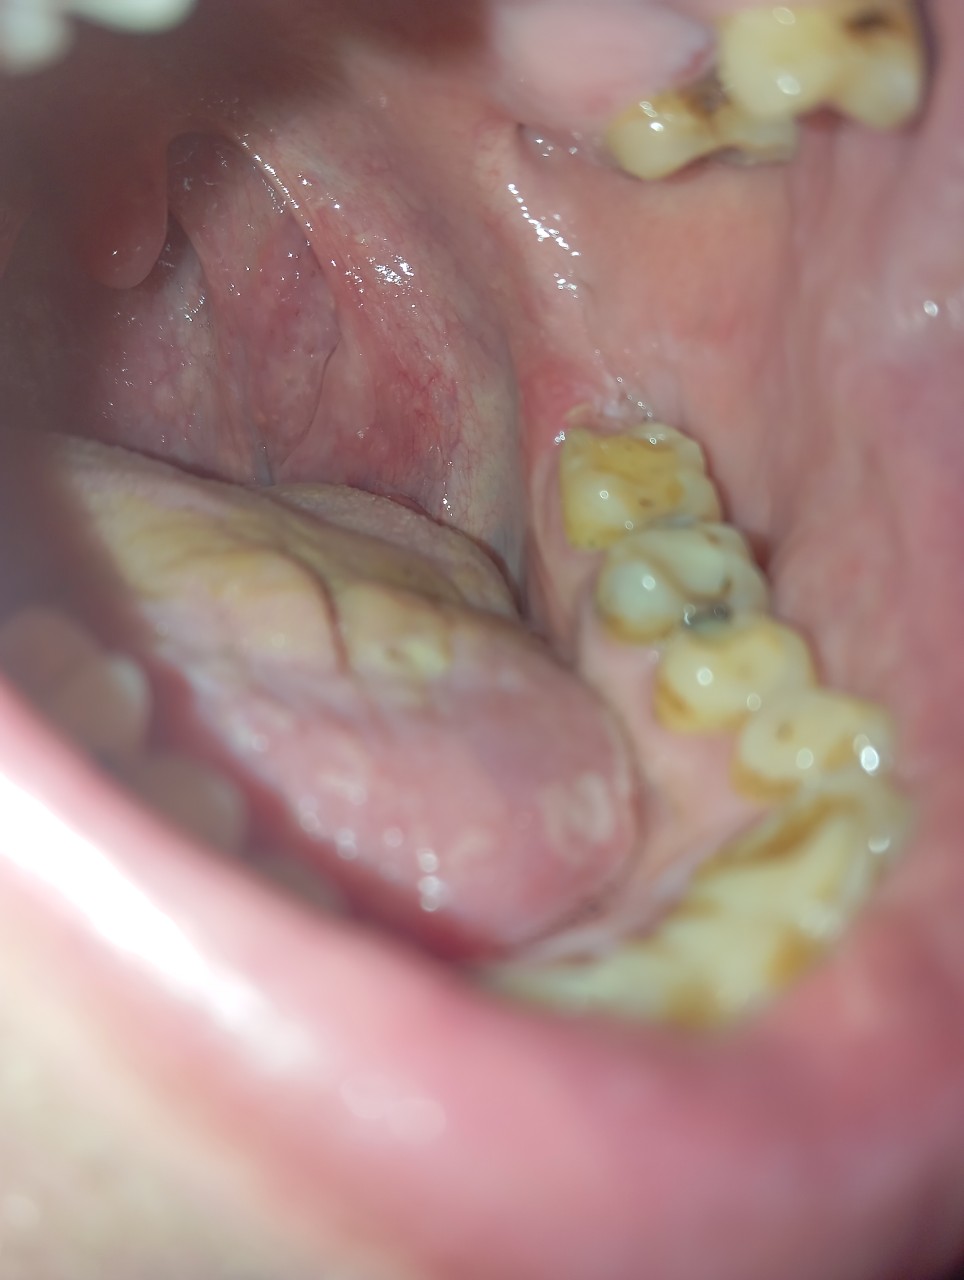

Вітаю, Добрый день. Неделю назад у меня начала болеть десна в нижнем ряду за седьмым зубом. Там как бы ранка Толи трещина и подпухло немного. Та восьмерка следит крепко. Мне 46 доктор говорил шо она уже не выйдет. Так вот через пару дней добавилась боль в шестом или седьмом зубе. Пульсирующая боль. Ночью не спал почти. Утром сегодня поехал к хирургу он удалил шестой зуб так как он плохой на снимке. Теперь я думаю решил ли я проблему, или это будет продолжаться и в е это из-за восьмёрки? Как думаете на снимке есть восполнение которое давало боль? Спасибо.